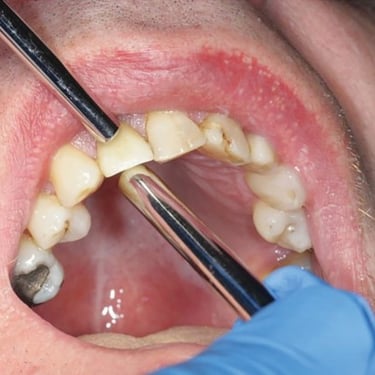

Fractura de la prótesis sobre implante

La fractura de la prótesis sobre implante es una ruptura o daño en la corona, puente o dentadura soportada por implantes.

Los pacientes pueden notar una prótesis suelta o dañada.

El tratamiento incluye la reparación o reemplazo de la prótesis afectada